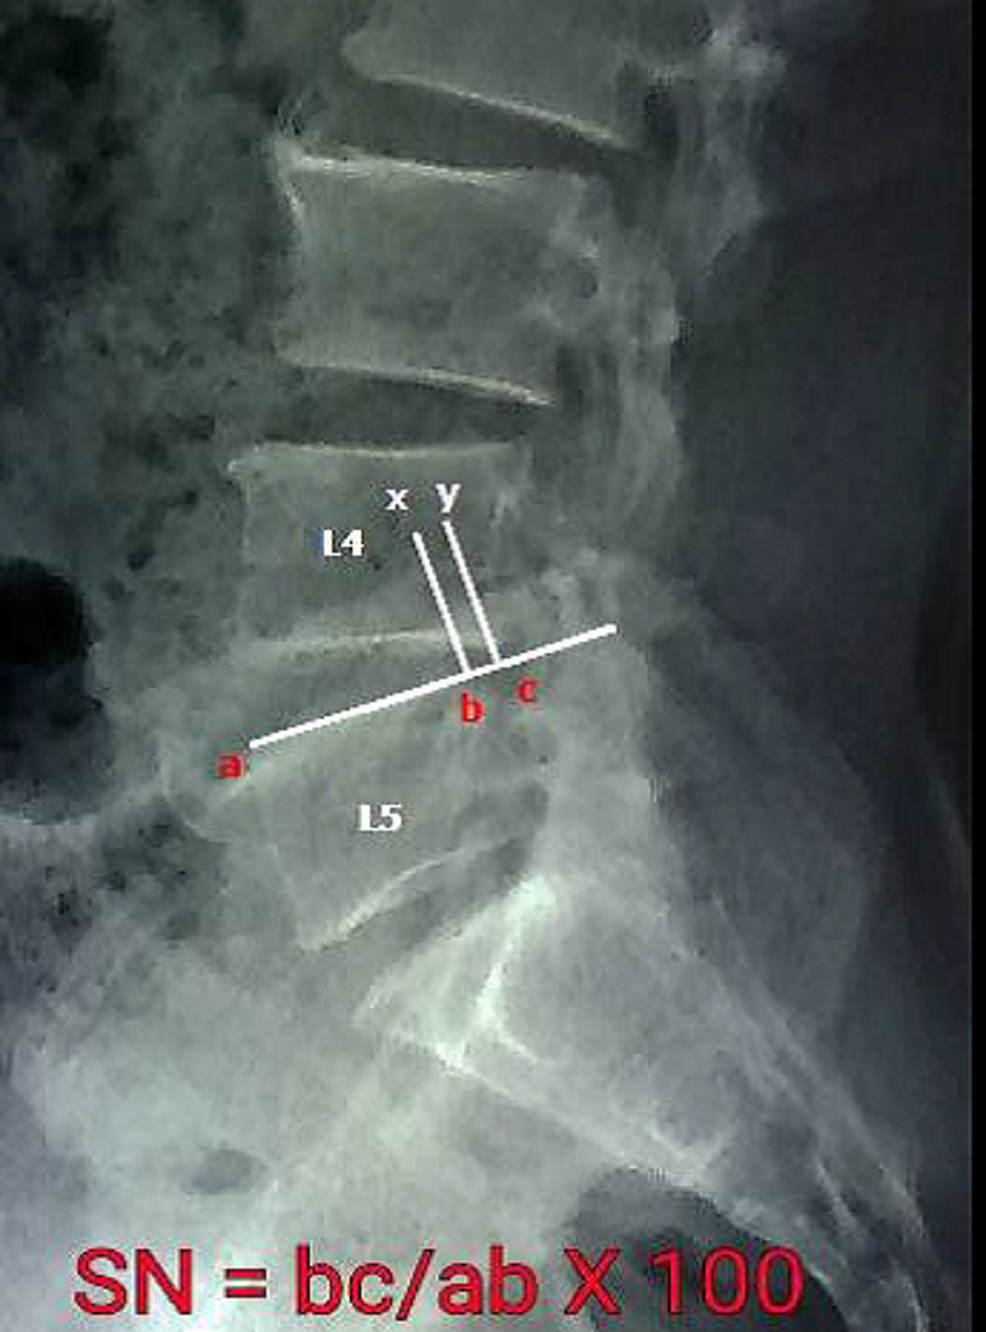

From www.researchgate.net

Xray of lumbar spine dynamic view showing instability at L4L5 What Is Lumbar Spine Instability In spondylolisthesis, one of the bones in your spine — called a vertebra — slips forward and out of place. adult spondylolisthesis in the low back. when one or more segments of the spine is deformed or out of place, the result is lumbar instability that often results in pain or discomfort due to increased pressure. spondylolisthesis. What Is Lumbar Spine Instability.